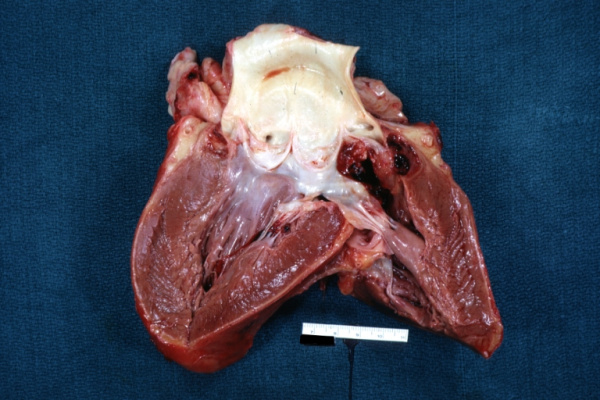

Предоперационное эхокардиографическое исследование выявило аневризму правого коронарного синуса с прорывом и формированием аорто-правожелудочковой фистулы, комбинированный аортальный порок с выраженным кальцинозом, тяжелым стенозом и недостаточностью, гипертрофию и дилатацию левого желудочка (конечный диастолический объем — 300 мл), снижение глобальной сократимости левого желудочка (фракция изгнания — 37%) на фоне диффузного снижения локальной, тяжелую трикуспидальную недостаточность, тяжелую легочную гипертензию. Порок сердца подтвержден данными МСКТ (см. рисунок). При КТ-коронароангиографии поражения коронарного русла не обнаружено. От проведения дооперационной терапии левосименданом мы вынуждены были отказаться по причине наличия у пациента частой желудочковой экстрасистолии и пробежек желудочковой тахикардии по данным мониторирования ЭКГ по Холтеру.

Аорто-правожелудочковая фистула (мультиспиральная компьютерная томография). ЛЖ — левый желудочек, Ао — восходящая аорта, ПЖ — правый желудочек, ЛС — легочный ствол. Стрелками обозначен диаметр аорто-правожелудочковой фистулы. Слева от фистулы визуализируется кальцинированный аортальный клапан.